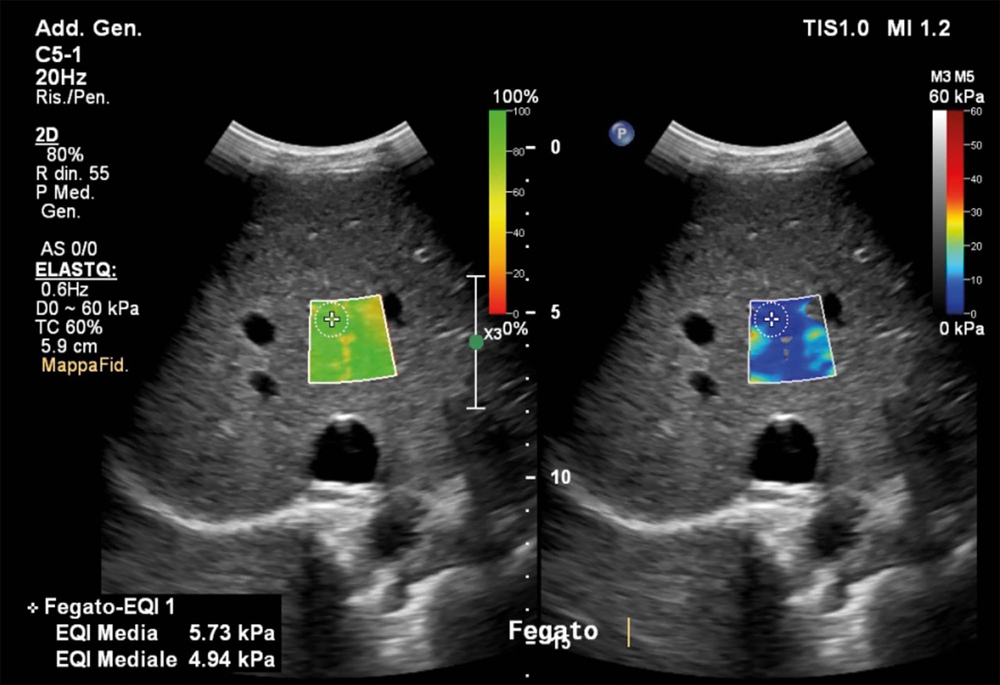

Una delle applicazioni più importanti è la valutazione della fibrosi epatica. Il fegato, in presenza di infiammazioni croniche come le epatiti virali e di steatosi, può sviluppare fibrosi, cioè una sostituzione del tessuto sano con tessuto cicatriziale più rigido. «L’elastosonografia shear wave ci consente di stimare la rigidità del fegato senza ricorrere alla biopsia epatica — spiega il dott. Ivona — offrendo una stima affidabile e ripetibile nel tempo». Questo permette di monitorare l’evoluzione della malattia, valutare l’efficacia delle terapie e individuare precocemente i pazienti a rischio di cirrosi, riducendo l’uso di procedure invasive. L’esame è indicato per chi soffre di epatite cronica B o C, steatosi epatica, epatopatie alcoliche o patologie autoimmuni del fegato.